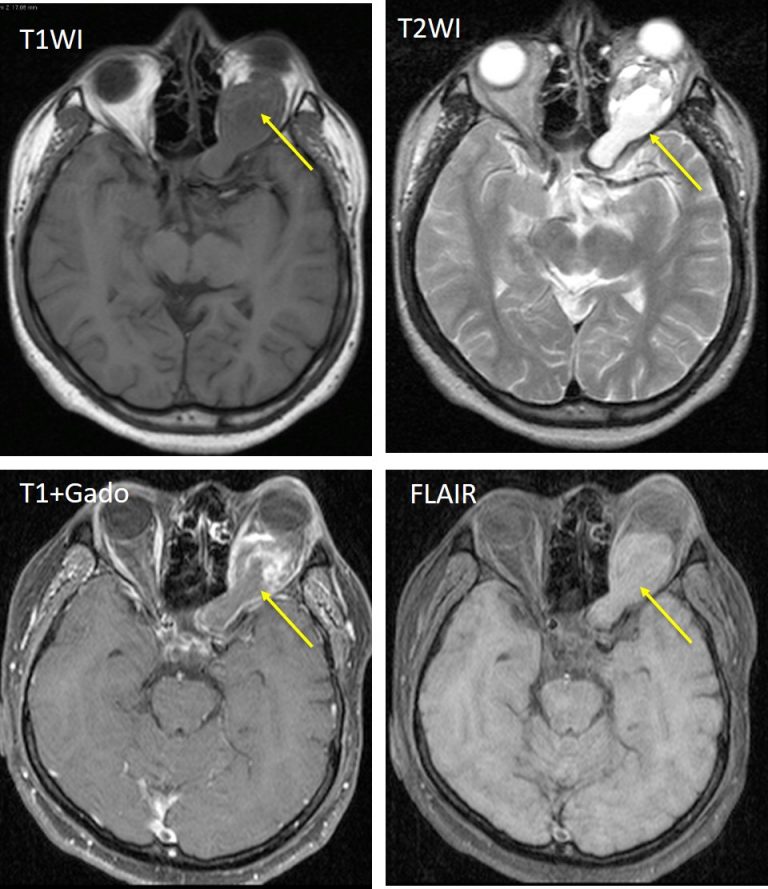

Contrast enhanced T1weighted axial resonance imaging of the Optic Nerve Parts Radiology optic neuropathy is a broad term and can result from a variety of causes. mri can show optic nerve compression by swollen extraocular. Intraocular (1 mm) (also called optic nerve head). emerging mri technologies that emphasize rapid acquisition should improve visualization of the optic nerve and facilitate accurate quantification of mri. the radiologic investigation of the. Optic Nerve Parts Radiology.

Optic nerve glioma Radiology Cases Optic Nerve Parts Radiology Intraocular (1 mm) (also called optic nerve head). The optic nerve head, the. emerging mri technologies that emphasize rapid acquisition should improve visualization of the optic nerve and facilitate accurate quantification of mri. the optic nerve anatomically starts from the optic disc and ends in the optic chiasm and comprises 4 distinct parts: imaging of the optic. Optic Nerve Parts Radiology.